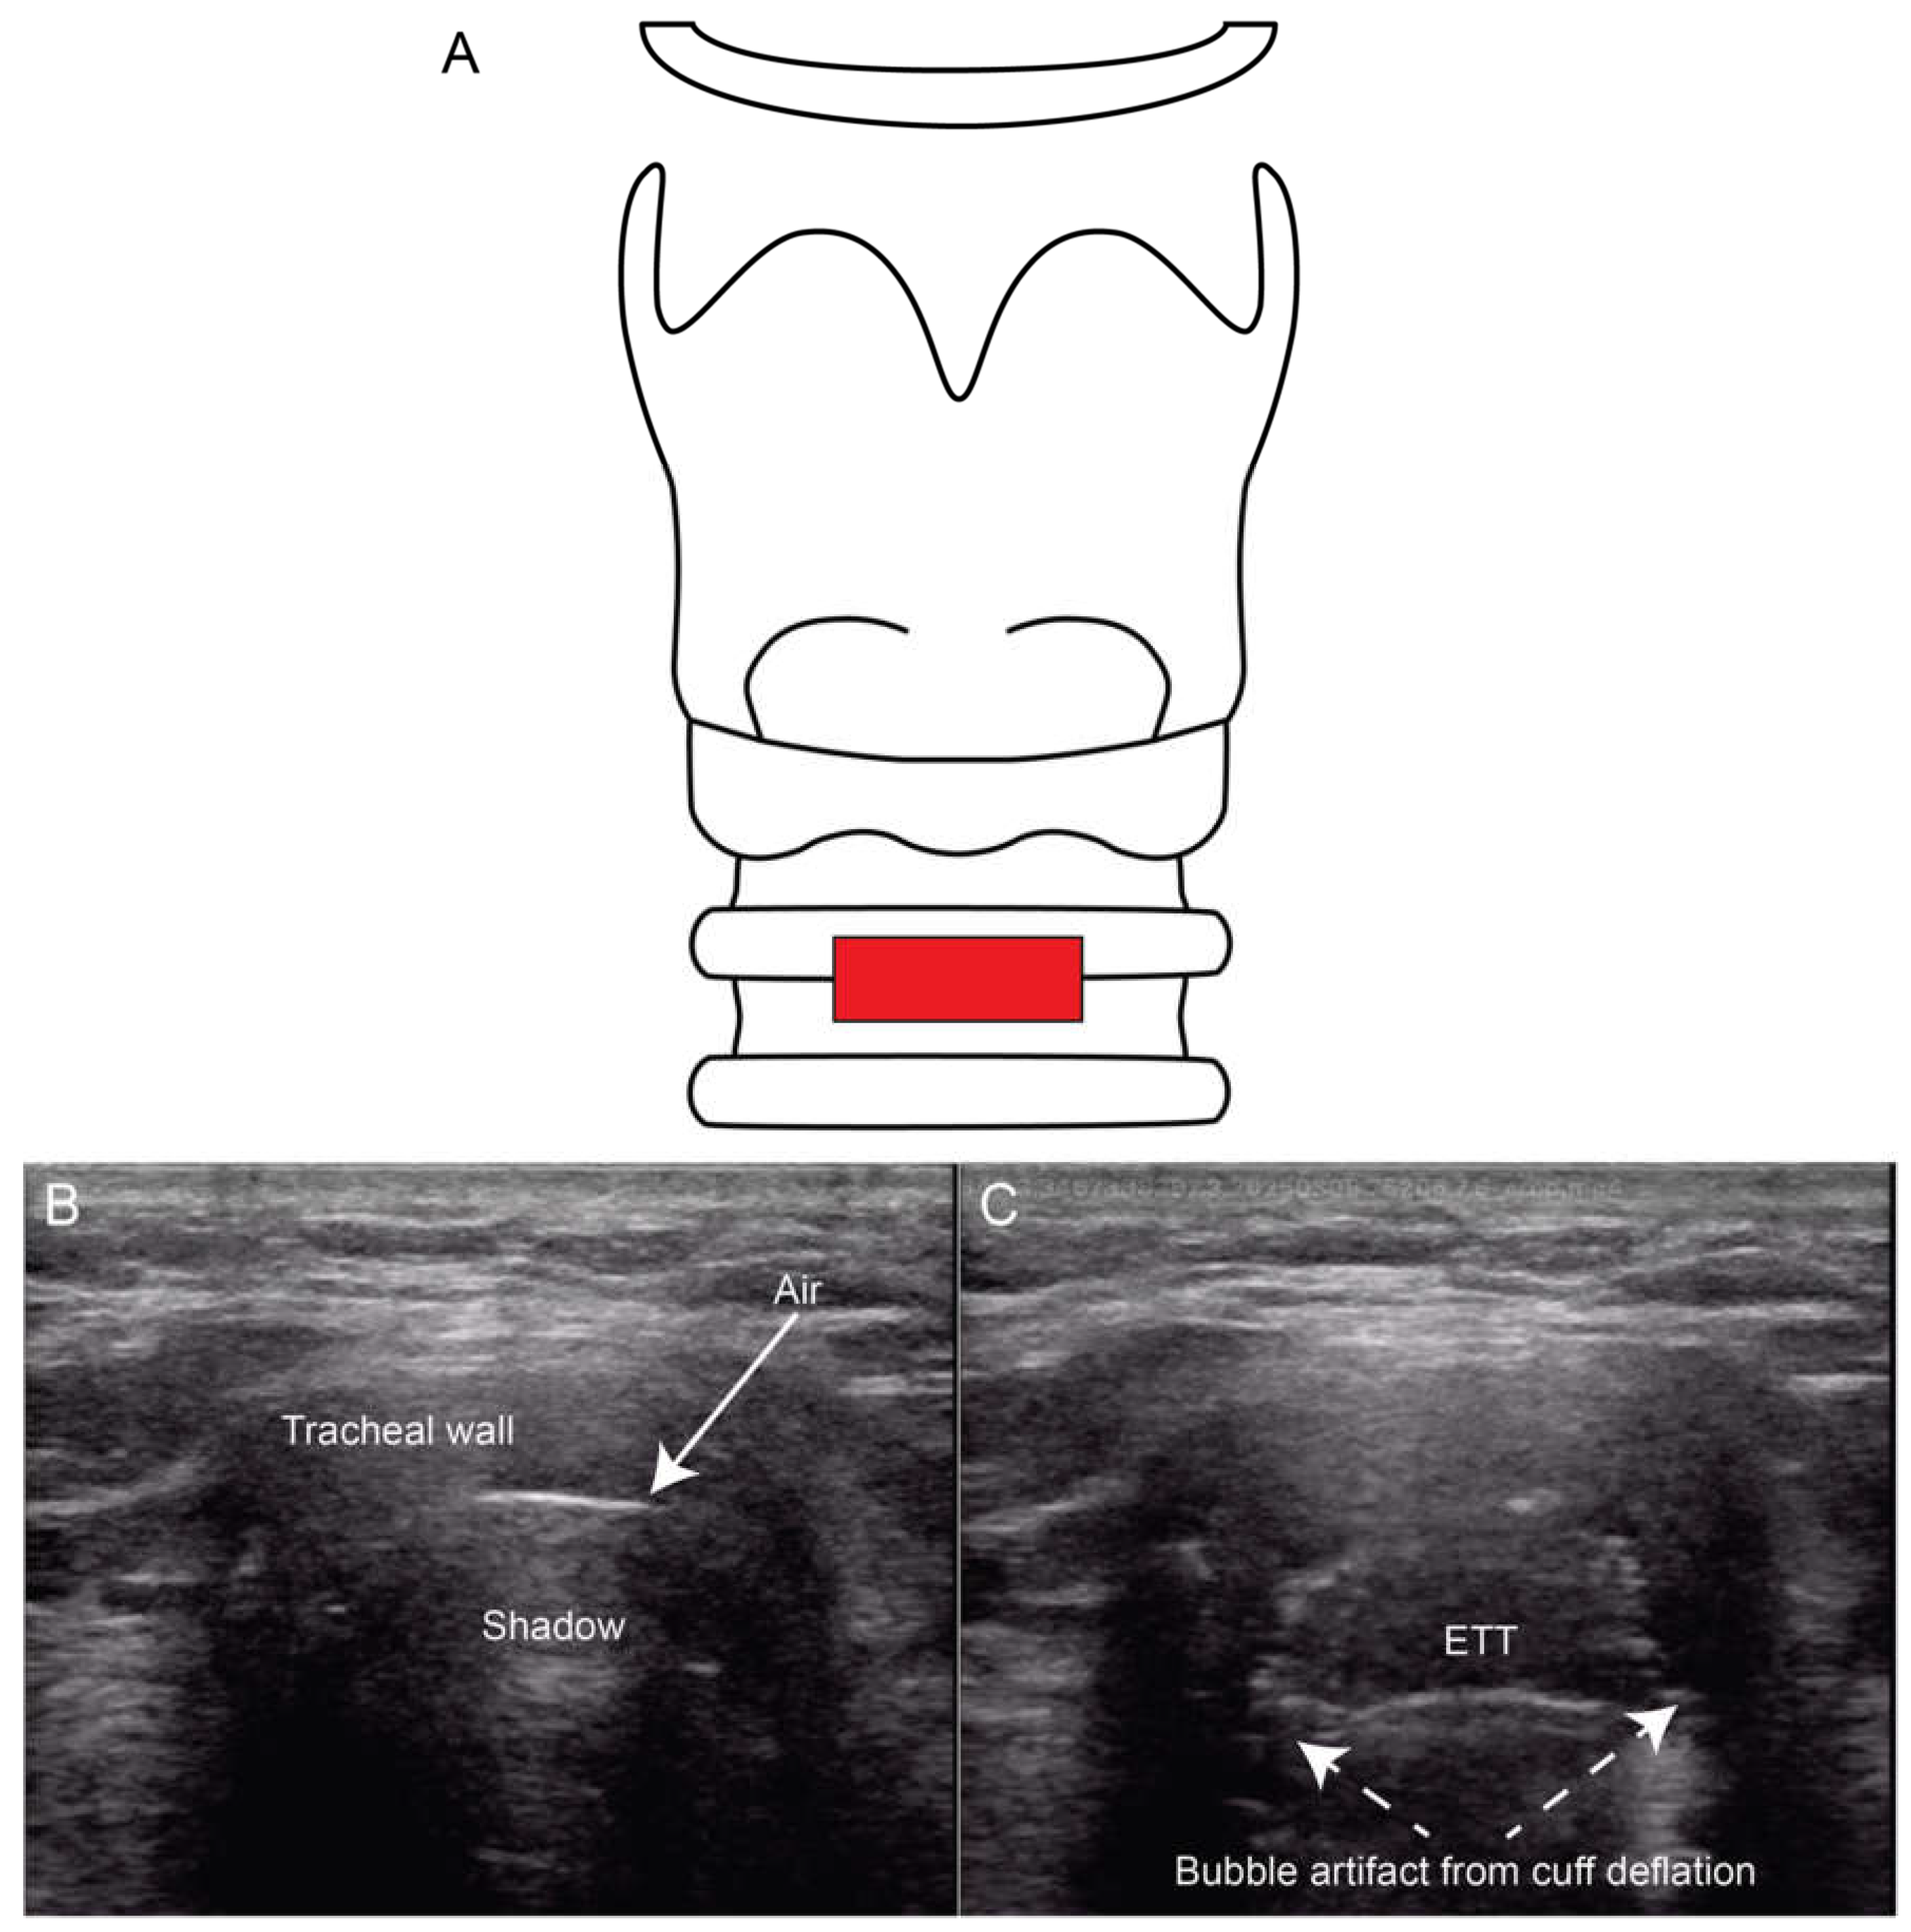

When performing endotracheal intubation (ETT), it is essential to confirm that the ETT is properly positioned in the trachea at the correct depth. Unrecognized misplacement in the esophagus can lead to life-threatening complications [25]. Traditional methods of ETT verification include auscultation of bilateral lung sounds which is unfortunately insensitive, CXR which can be slow and not always available, and quantitative capnography which cannot assess ETT depth or evaluate for right mainstem intubation. Ultrasound of the trachea and lungs can verify both the tracheal placement and location of the ETT after intubation. Utilizing a linear probe placed across the distal neck (Figure 7B-C), clinicians can visualize a malpositioned ETT in the esophagus as a second air-filled structure lateral to the trachea, mandating immediate removal and tracheal placement. To directly visualize the ETT in the larynx in the same view, studies have shown that inflating and deflating the ETT cuff rotating the ETT in the trachea and placing color Doppler over the cuff may be useful approaches [25,26,27].

Figure 7. Ultrasound images of the anterior neck demonstrating ETT placement. A transverse view at the suprasternal notch (Panel A) allows identification of the trachea (Panel B) and confirmation of intratracheal ETT placement using cuff inflation and deflation to generate bubble artifact (Panel C).